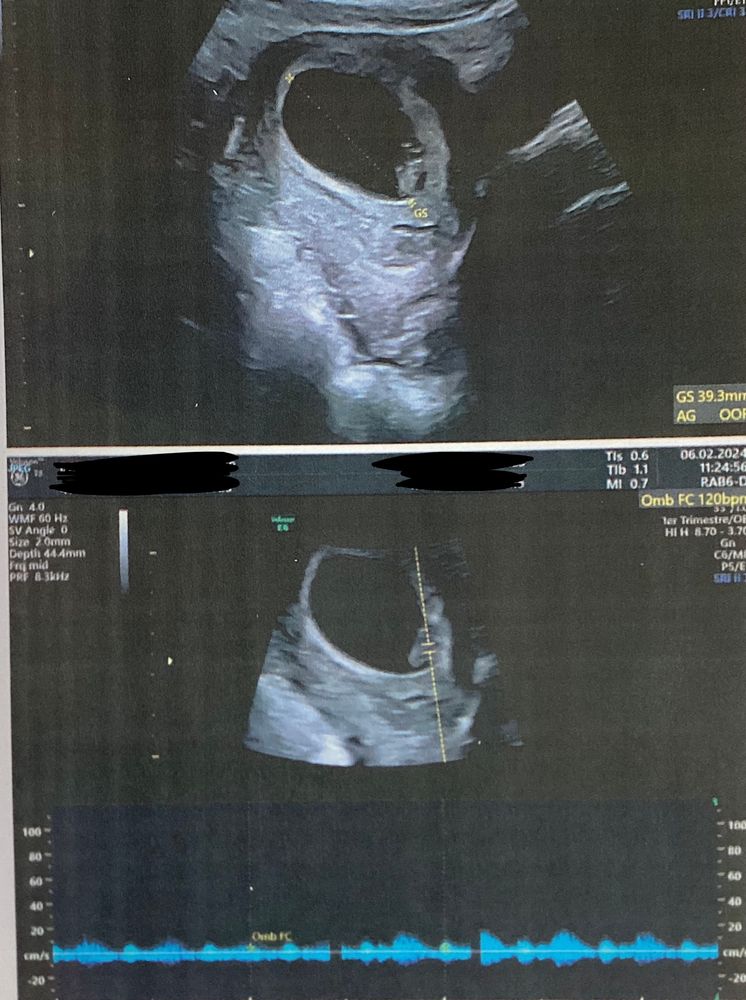

Сегодня впервые увидела свою крошку 🥰 и даже услышала сердечко❤️ прослезилась :) мне повезло , что мой доктор оказалась из Грузии и говорит на русском 😃 чудо какое ☺️ она сказала , что ещё рано конечно о чем то говорить и ждёт меня 7 марта с анализами и только 13 марта будут все досконально проверять на аномалии и тд 🤞🏻 так долго ждать 🥲 мы боимся радоваться и никому не рассказываем ( ещё меня мучает токсикоз 🤪 есть не могу скоро исхудаю совсем😅 кто так же ? как справляетесь с токсикозом ?

Оксана, по моим подсчетам у меня 7 неделек всего . Что такое ктр сейчас только погуглила 😄 доктор вроде что-то про 8 мм говорила может это оно :) про сердцебиение тоже ничего не сказала , просто дала быстро послушать и всё:) вся конкретика только в марте 🤪 буду надеяться на лучшее ☺️🤞🏻

06.02.2024